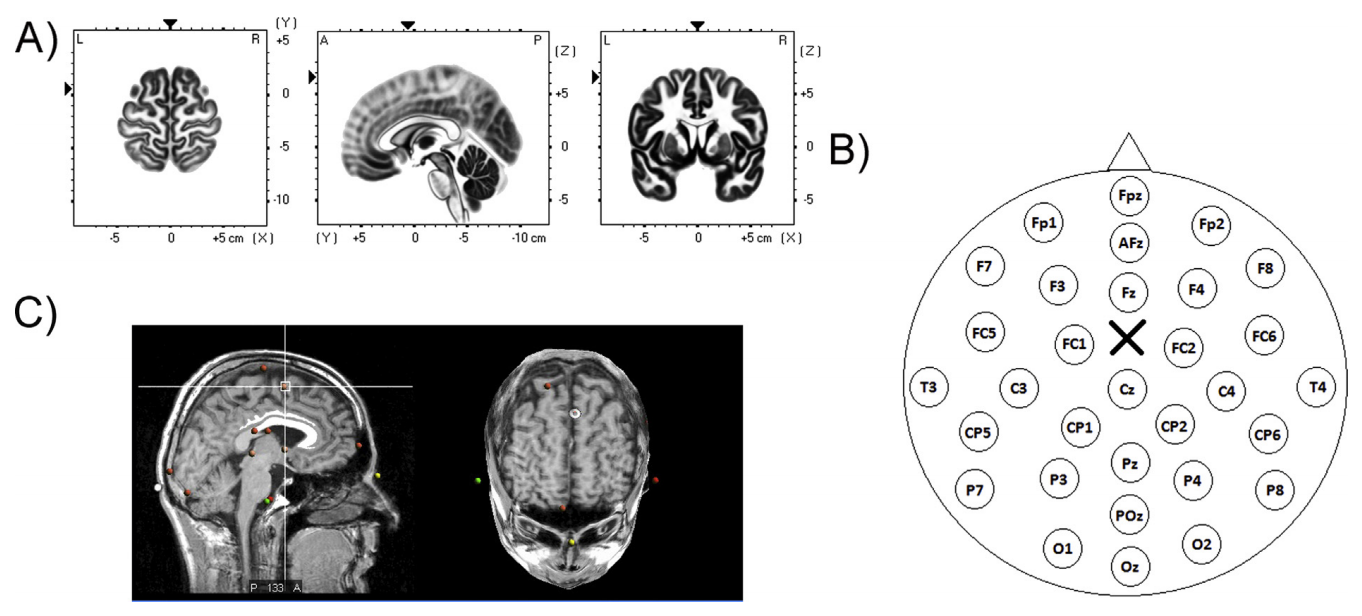

神经导航系统(Visor-2, ANT NEURO B.V., The Netherlands)用于颅磁刺激/脑电记录时线圈的正确位置。将脑电图帽放置在头皮上,带有用于检测鼻点/双耳穴的传感器。磁共振模型用于重建:每个参与者的头皮表面被复制以适应模型。根据Zhang et al., (2012; MNI坐标:x = 0, y = 6, z = 66;图1),并标记在脑电帽上。选择的是允许刺激双侧辅助运动区(supplementary motor area, SMA)复合体(即适当的SMA和前SMA区域)的皮质目标。

图1. 刺激点和记录的脑电图电极的表征

在SMA中选择的皮质靶点坐标(Talairach: x = 0, y = 9, z = 60;MNI: x = 0, y = 6, z = 66)由sLORETA大脑解剖模型(A)和神经导航获得的共振模型(C)表示。记录的电极也被指示并叠加在头皮模型(B)表示头皮上对应的刺激点。